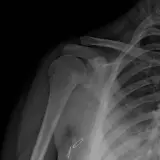

Over 2,100 interactive radiology cases, curated by radiologists for your level of training. Scroll, window, and view cases full screen — just like on PACS. Click linked findings in each writeup to jump straight to them on the image. Cases include sample reports, a focused discussion section, original illustrations, and videos.

完全交互式病例,配备您在 PACS 上期待的各项工具——滚动、调窗、缩放、平移、测量、ROI 和全屏模式。

丰富的标注直接在病例图像上突出关键发现。点击病例讲解中的关联发现,即可跳转至其在扫描上的精确位置。